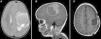

Atypical teratoid rhabdoid tumors (AT/RT) of the central nervous system are rare, very aggressive embryological tumors, typically diagnosed in young patients and having a low survival rate after diagnosis. The aim of this study was to emphasize, based on the latest results in the literature, the need for protocols for multidisciplinary treatment in these patients.

ResultsTwo of our 3 cases (supratentorial and spinal tumors) did not show any progression of the disease after long follow-up, in contrast with most of the cases available in the literature. The second patient had a shorter survival.

ConclusionsPatient age at the time of diagnosis, supratentorial location of the mass and fewer complications with adjuvant treatments seem to be factors yielding good prognosis for AT/RT tumors. In agreement with the latest international protocols, multidisciplinary treatment is the ideal treatment, consisting of radiotherapy and chemotherapy after complete tumor resection.